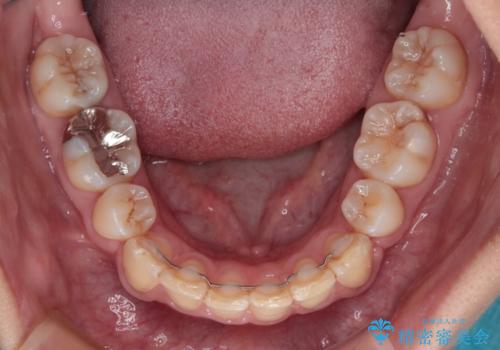

抜歯矯正により、口元の印象だけでなく、横顔の印象も大きく改善されました。